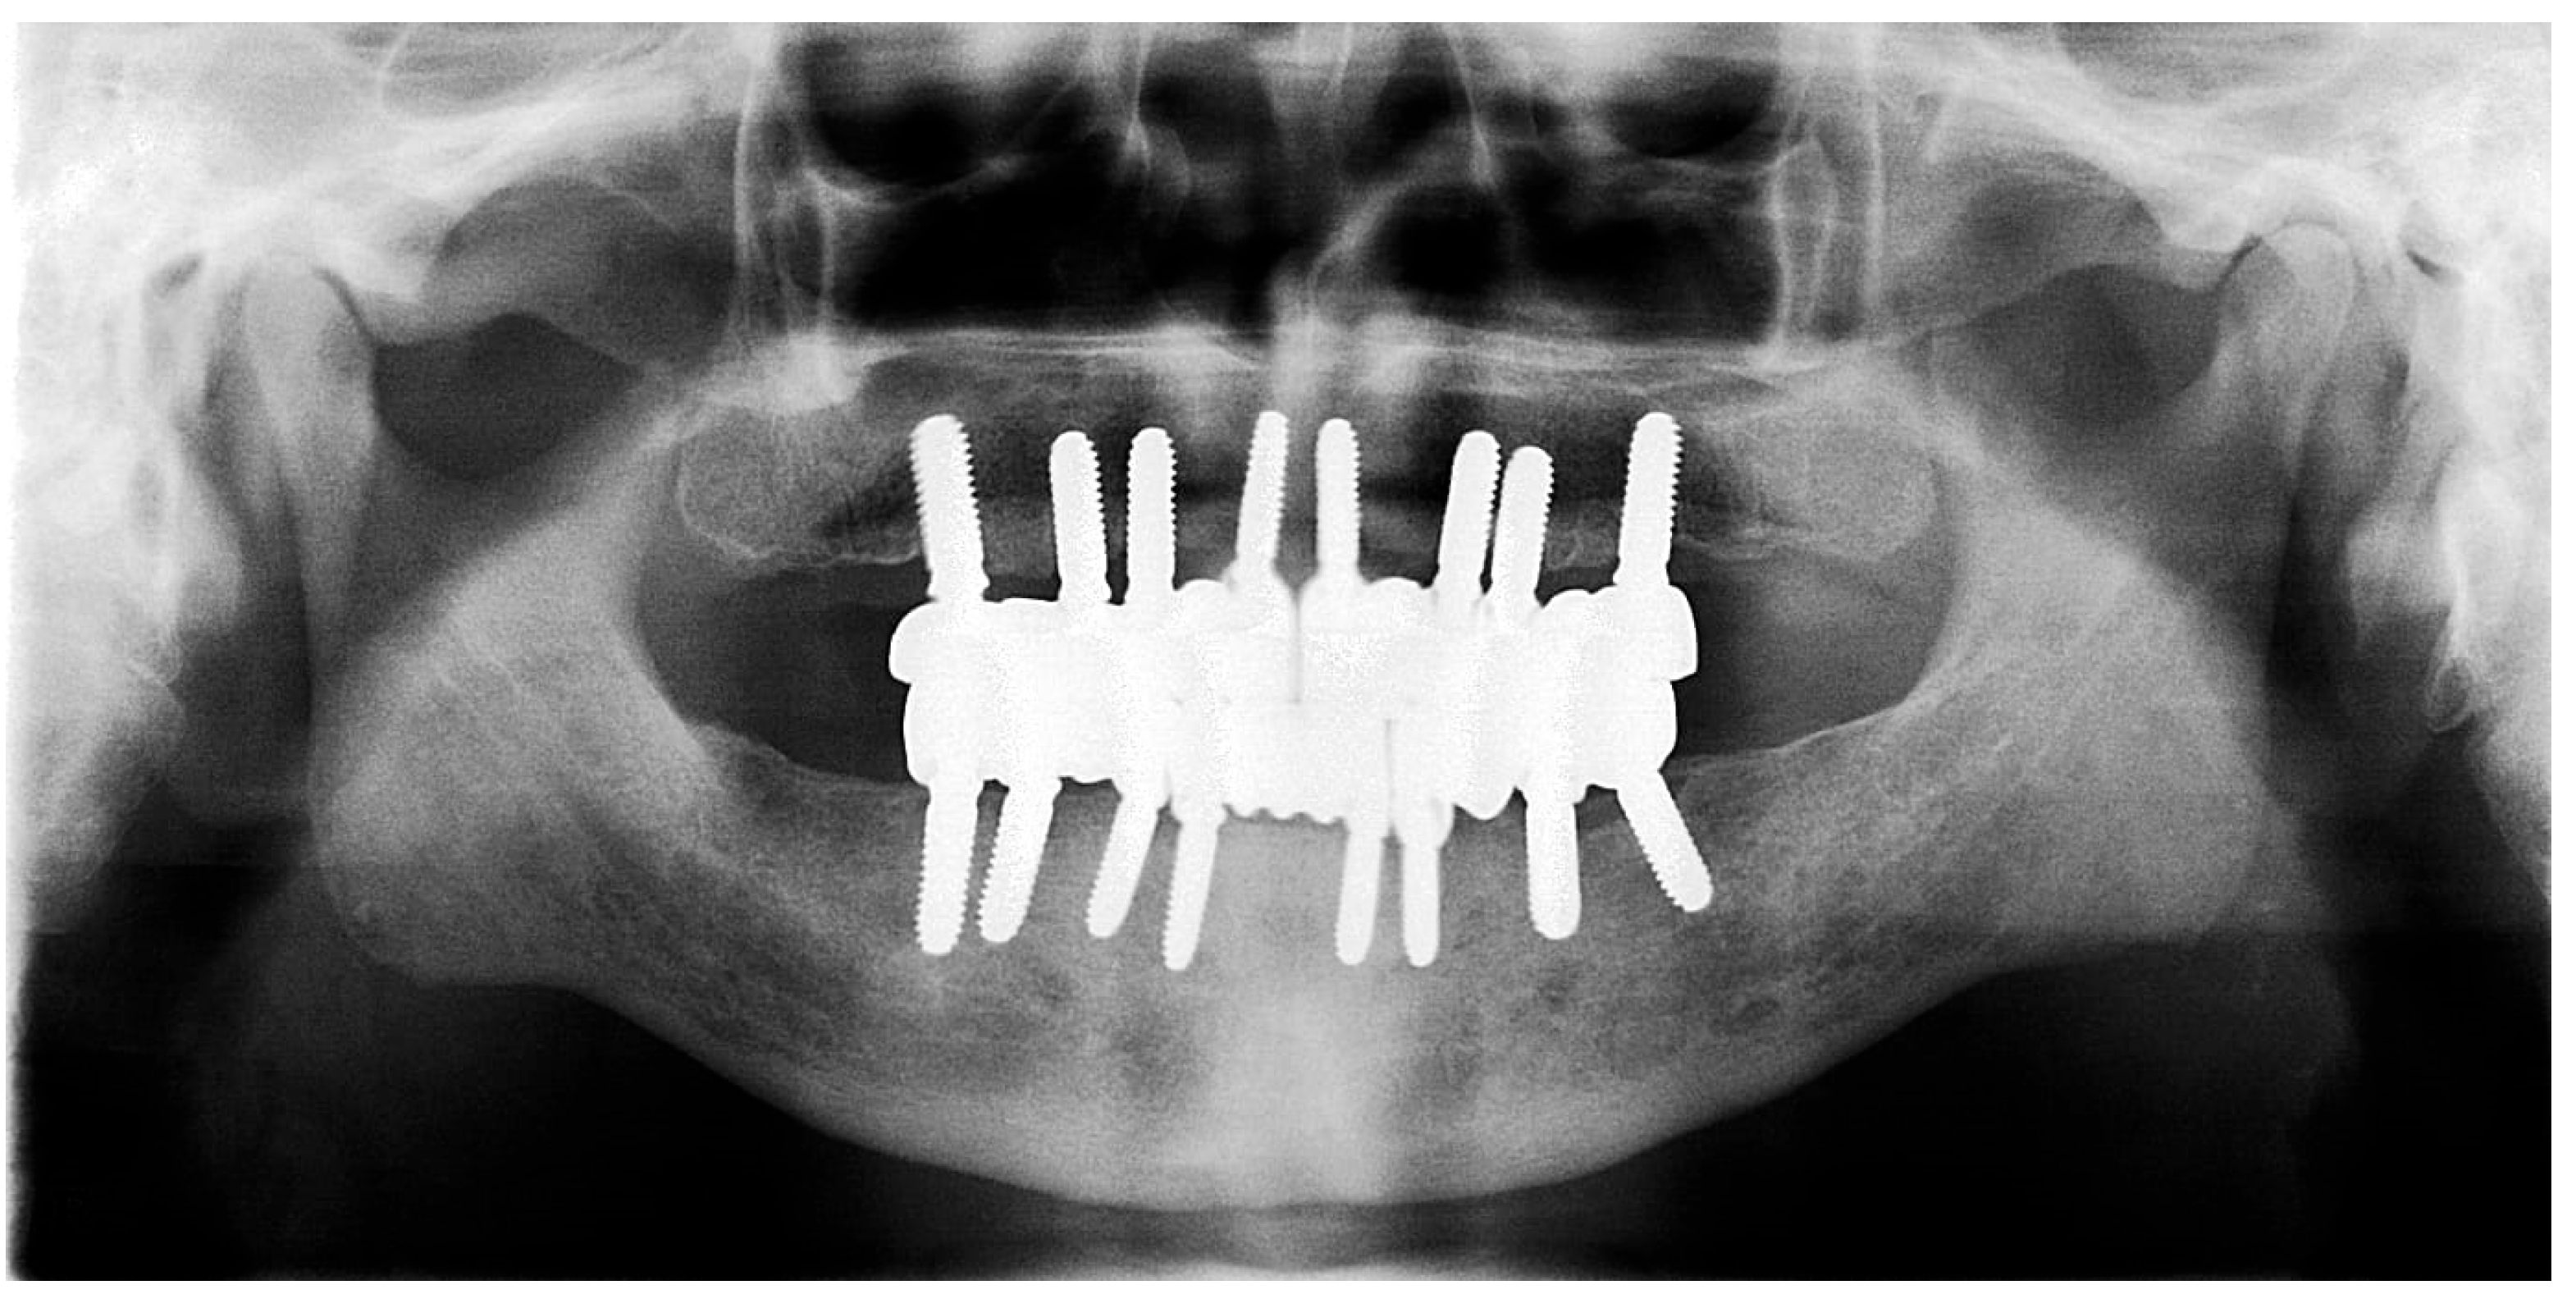

Figure 15. Panoramic X-ray showing the final prostheses (taken 21 November 2023).

The restoration plan involved placing a bridge that connects the central incisors to the canines, along with an additional bridge spanning the first premolar to the first molar on each side of the maxillary arch. In the mandibular arch, the plan included three bridges: one connecting the lateral incisors bilaterally and another bridging the canines to the second premolars and first molars on each side (Figure 14 and Figure 15). Placing was confirmed using Panoramic radiographs obtained using the PantOs DG XP panoramic dental X-ray system (Fona S.r.l., Assago, Italy; CE 0051). The unit operates on a 230 V, 50/60 Hz input line with an 8 A fuse. Standard panoramic exposure parameters were applied (90 kVp, 10 mA, exposure time 14 s) following the manufacturer’s safety recommendations. A trained radiology technician performed all scans, and patient positioning was standardized using the built-in cephalostat support and light-beam alignment to ensure reproducibility of serial images.

Radiographic evaluation in this study was limited to qualitative and linear assessment of crestal bone stability. While X-rays provide reliable detection of changes in marginal bone level, they cannot quantify bone mineral density (BMD). Hence, the radiographs presented here serve as indicators of implant stability rather than bone density evaluation. Quantitative assessment of bone density would require modalities such as CBCT voxel analysis or dual-energy X-ray absorptiometry (DEXA), which were not part of this retrospective case.